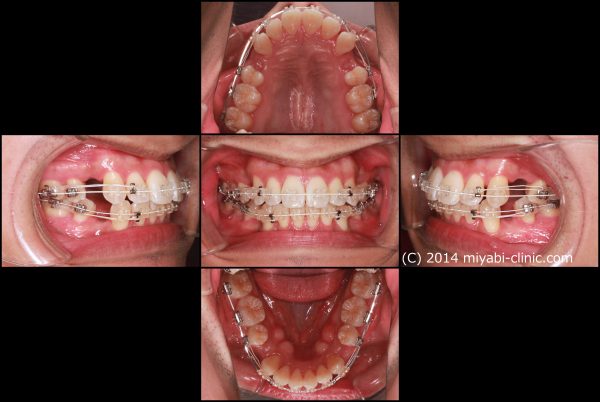

口もとの出っ張りと、”出っ歯”を治すために上下顎左右の小臼歯抜歯を行い、前歯を後方に移動させました。

口ゴボ治療中

2022年の9月13日にスタートして 、2024年の10月29日に 終 了 しました。